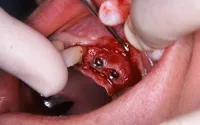

差し歯を除去した写真です。

歯茎を切開すると、上顎に大きな空洞がありインプラントを埋め込む為の骨がありません。

造骨材で骨を作っている写真です。